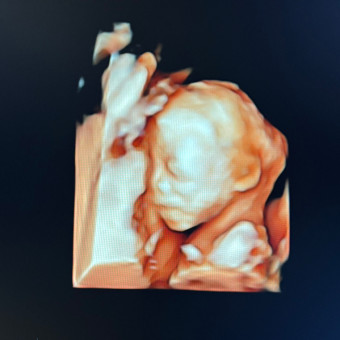

Baby Calvin #2

Marisol Calvin

February 18, 2026